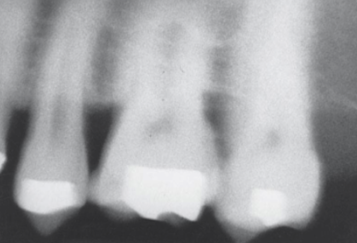

Foreshortening

What it looks like:

Teeth appear short and stubby.

Cause:

Excessive vertical angulation.

Fix:

Reduce vertical angulation.